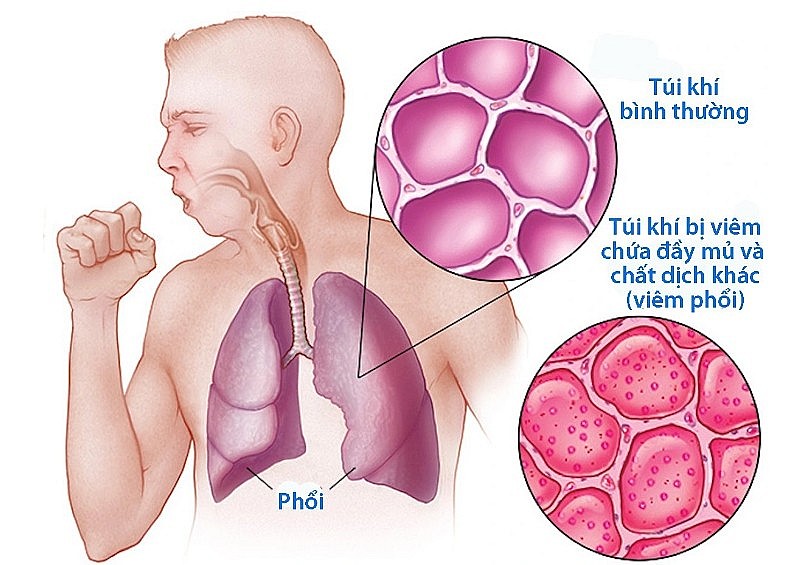

Viêm phổi là bệnh lý nhiễm trùng hô hấp nghiêm trọng thường gặp do vi khuẩn, virus hoặc nấm gây ra. Bệnh viêm phổi có thể gặp ở mọi lứa tuổi và xảy ra quanh năm nhưng hay gặp nhất vào mùa đông xuân. Nguyên nhân là do vào mùa đông nhiệt độ xuống thấp, sức đề kháng của con người bị giảm sút, ô nhiễm không khí chính là điều kiện thuận lợi để các loại virus, vi khuẩn sinh sôi phát triển mạnh, làm cho bệnh viêm phổi diễn biến phức tạp. Trong đó, virus cúm, vi khuẩn phế cầu là những tác nhân thường gặp nhất. Hiểu rõ điều này sẽ giúp chúng ta tìm ra mẹo kiểm soát bệnh viêm phổi mùa đông hiệu quả.

Thời tiết lạnh sâu, hanh khô hoặc độ ẩm quá cao kèm theo chất lượng không khí liên tục ở ngưỡng báo động chính là những mối đe dọa hàng đầu đối với sức khỏe của lá phổi vào mùa đông. Trong đó, viêm phổi là một trong những tình trạng phổ biến nhất ở người lớn và trẻ em.

Người bị viêm phổi thường xuất hiện các triệu chứng đặc trưng như sốt cao, sổ mũi, nghẹt mũi, ho khan, ho có đờm,... Ở những đối tượng đặc biệt như trẻ sơ sinh hay người mắc bệnh lý nền hen, tiểu đường, các triệu chứng này có thể nặng nề hơn. Nếu không điều trị đúng cách có thể gây ra nhiều biến chứng nguy hiểm.